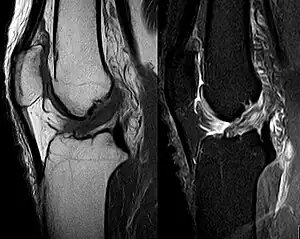

Medical imaging

Though clinical examination in experienced hands can be accurate, the diagnosis is usually confirmed by magnetic resonance imaging, which provides images of the soft tissues like ligaments and cartilage around the knee.[1] It may also permit visualization of other structures which may have been coincidentally involved, such as the menisci or collateral ligaments.[30] An x-ray may be performed in addition to evaluate whether one of the bones in the knee joint was broken during the injury.[9]

MRI is perhaps the most used technique for diagnosing the state of the ACL, but it is not always the most reliable technique as the ACL can be obscured by blood that fills the joint after an injury.[31]